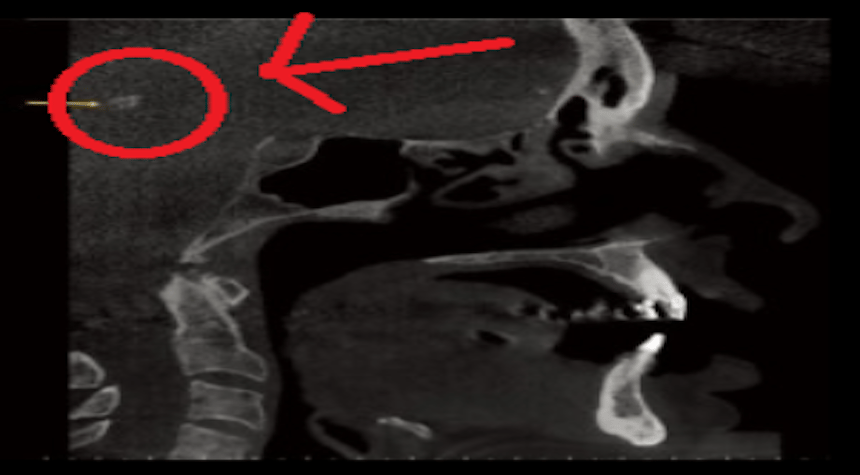

Look at this scan of a person’s skull…

The red arrow is pointing to a small speck in the middle of the brain.

This speck is a danger to the human brain that 99.99% of doctors don’t check for…

Yet this speck is like a silent “Alzheimer’s Factory” in your brain.